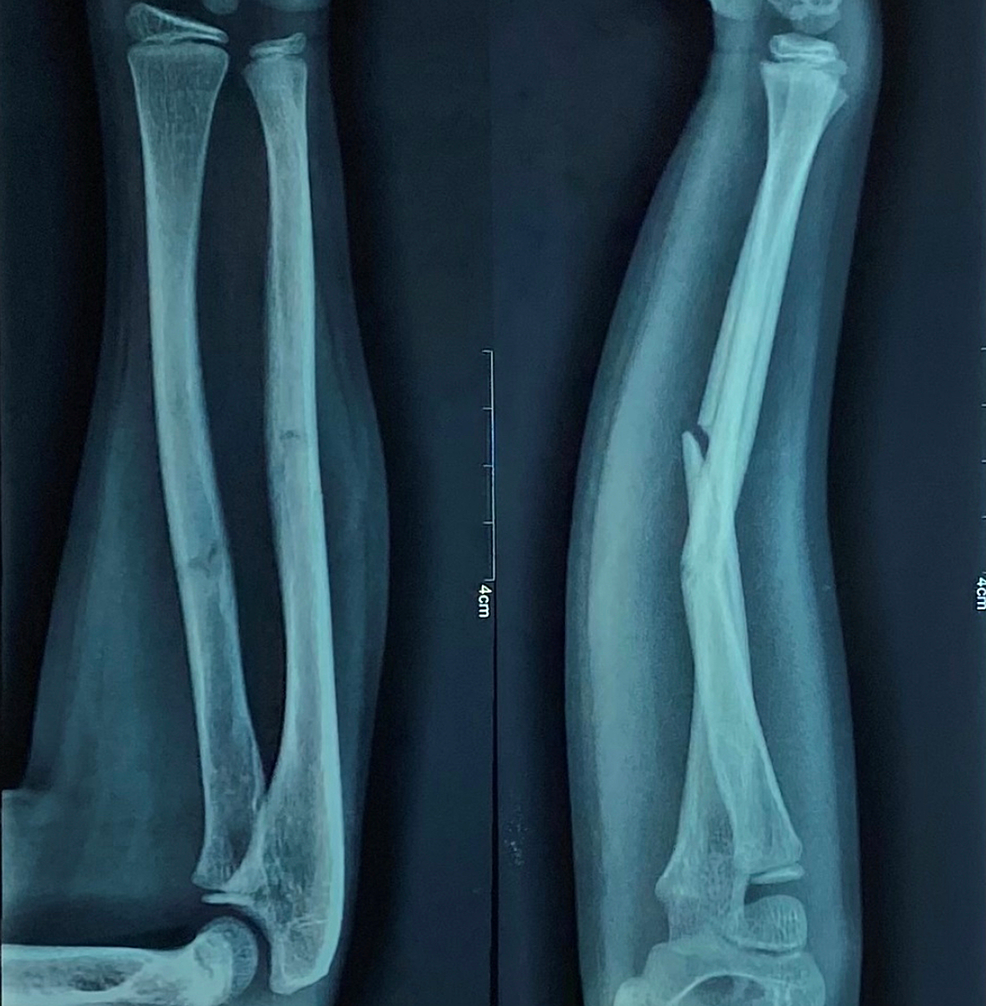

Pre-operative antero-posterior (AP) and lateral x-ray were taken (Figure 1). Adequate sedation was given to the patient. Fracture was reduced by the standard technique of axial traction manipulation. Reduction was confirmed radiologically by image intensifier and if found satisfactory, cast application was done (Figures 2, 3).

The above-elbow cast was put after proper padding, with elbow joint in extension and forearm in the most stable position (Figure 4). A cast index = 0.7 or less, calculation of which was done by dividing inner sagittal width of cast by inner coronal width of cast at fracture level, decreases fracture re-displacement risk. If reduction was not found to be acceptable, the process was repeated under general anesthesia with the help of a C-arm.

Antero-posterior (AP) and lateral view x-rays were recorded at two weeks post-reduction (Figure 5) and if no re-displacement was found, the cast was kept for four to six weeks and repeat radiographs were taken at four and six weeks and cast was removed (Figure 6). Radiographs were assessed for any angulation of the union site to assess for malunion. Clinical examination was performed three and six weeks after the removal of cast to assess the movement of the elbow and forearm. Stiffness of the elbow joint was assessed. The results were compared with the results of previously published results of casting of forearm fractures in flexion to determine the efficacy of casting.